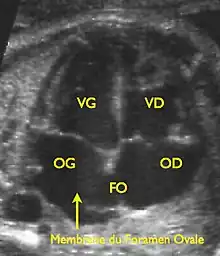

Le foramen ovale est un passage « en chicane » entre les deux constituants principaux de la cloison inter-auriculaire, le septum primum et le septum secundum, faisant communiquer les deux atriums. Il tend à être fermé par une membrane (« la membrane du foramen ovale ») qui n'est maintenue en position ouverte que par la différence de pression régnant dans les atriums.

Cœur fœtal.